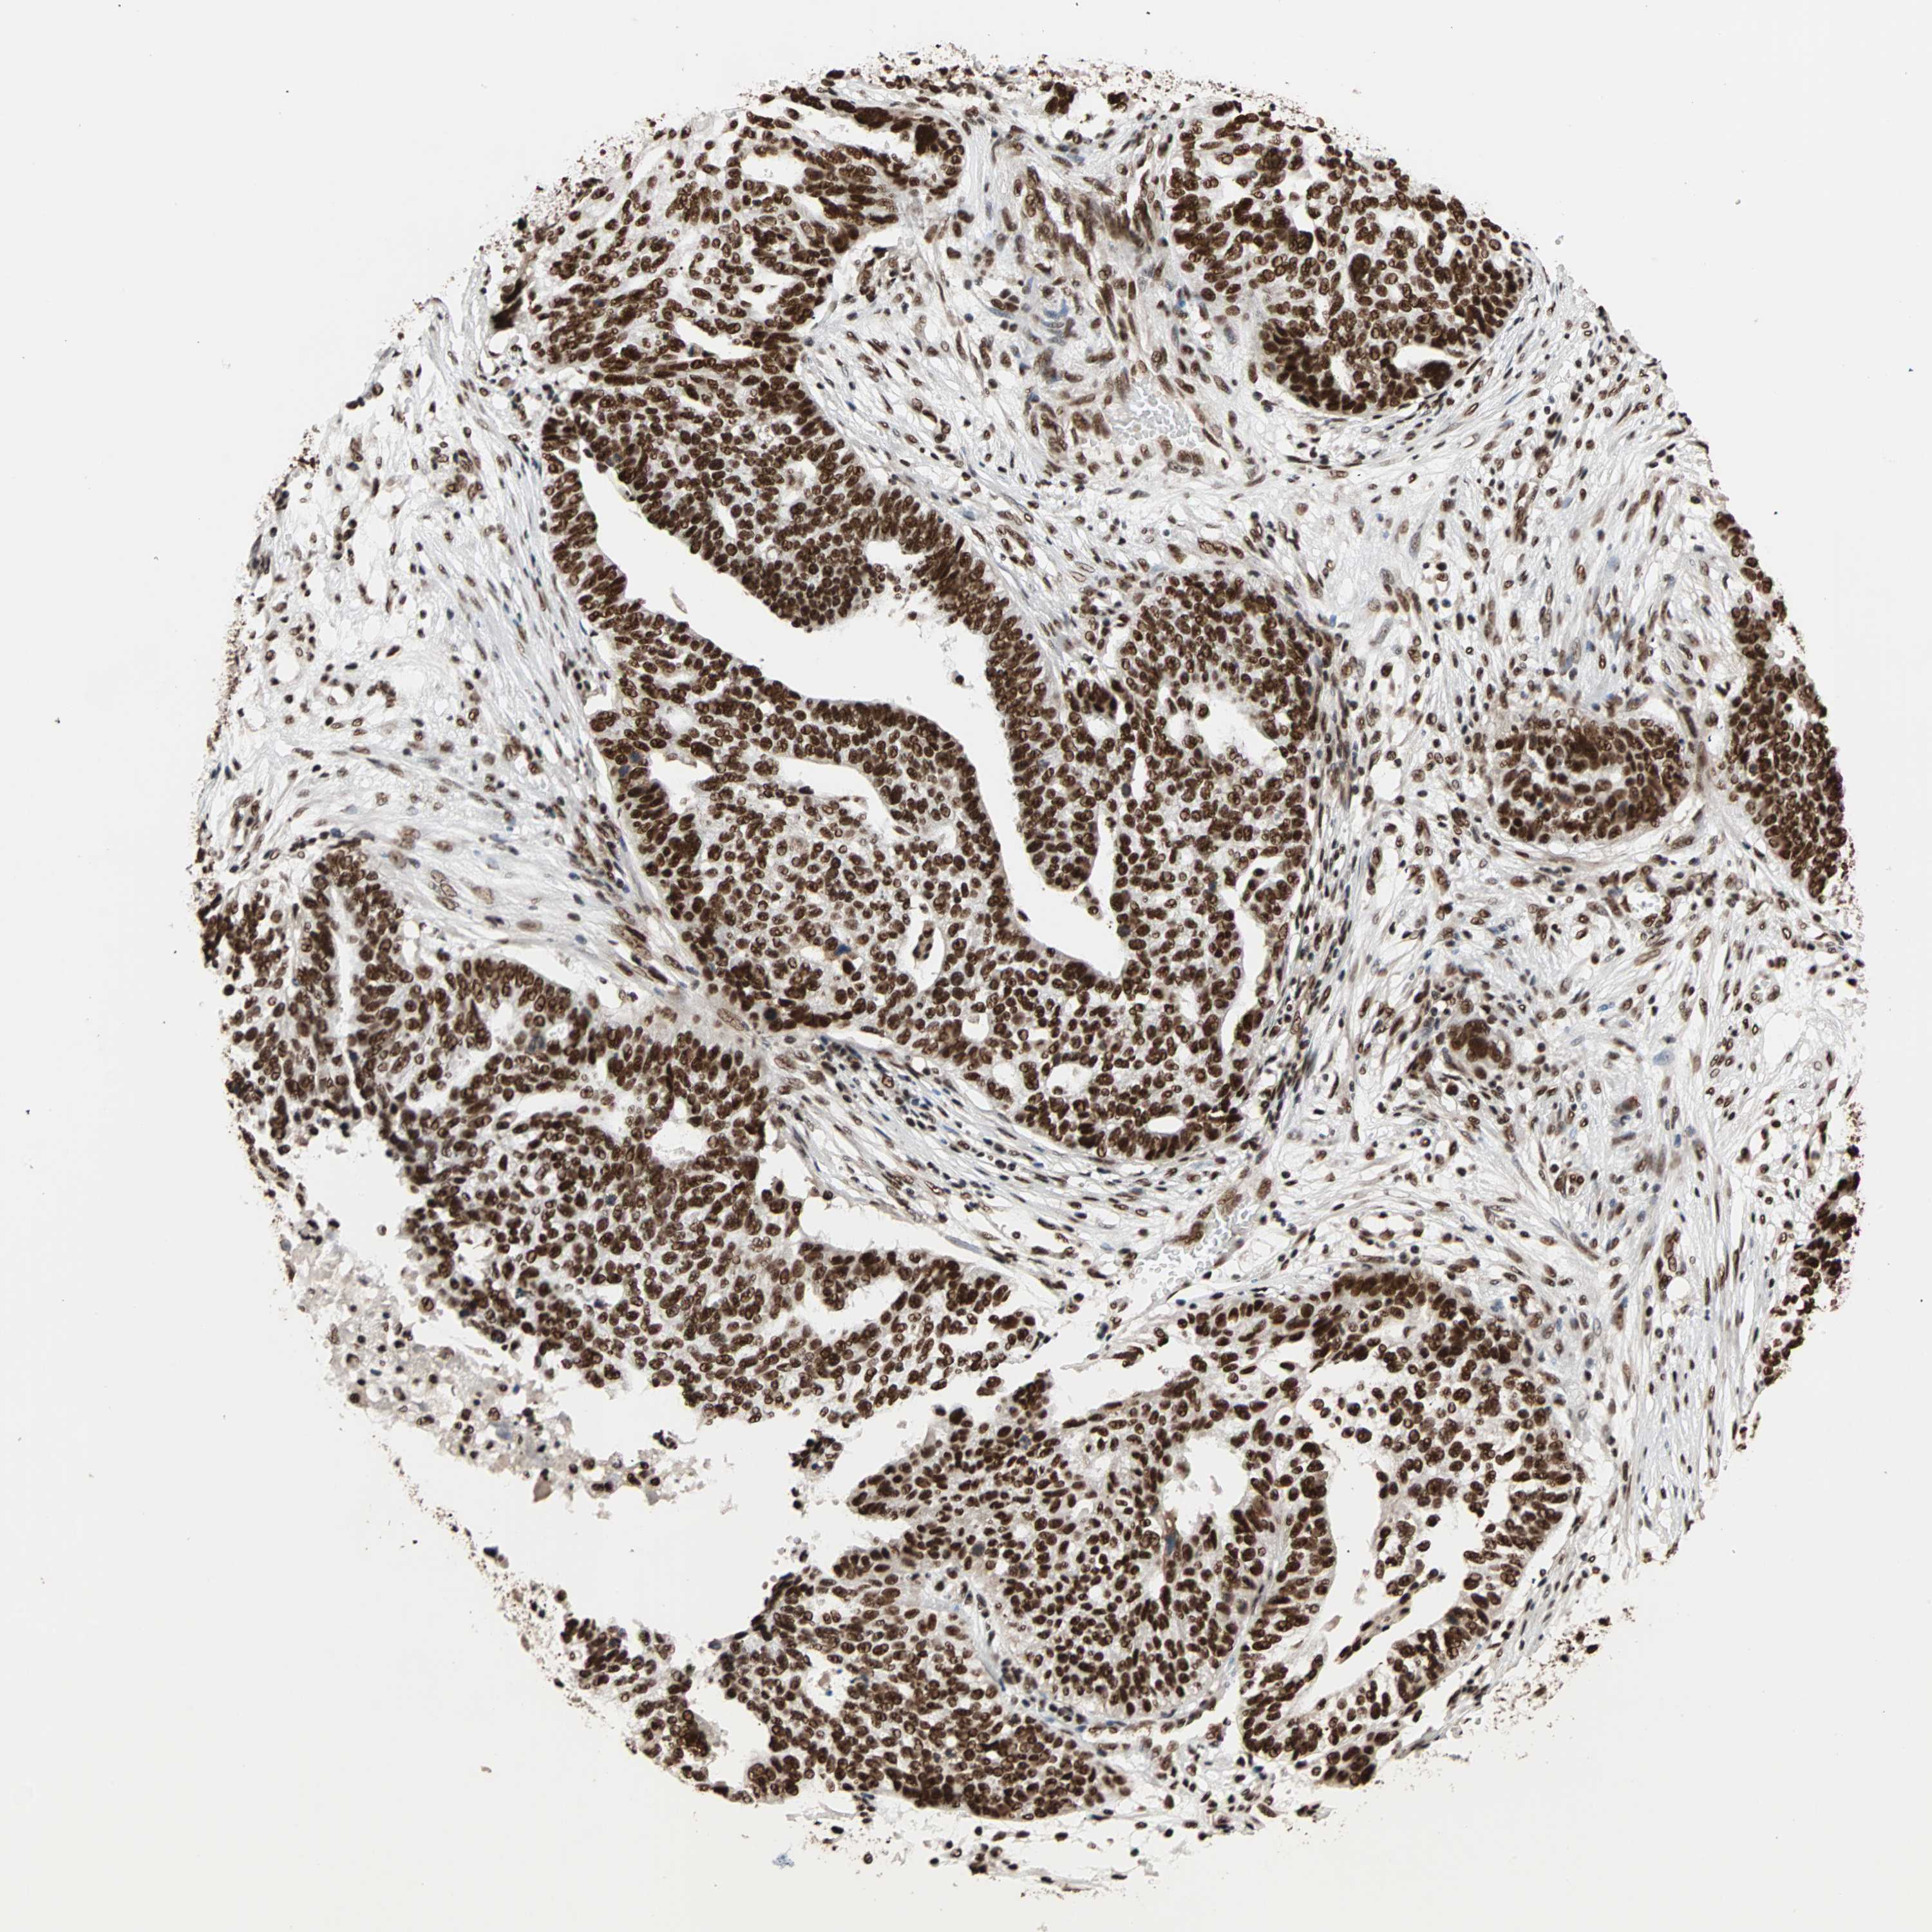

OVARIAN CANCER - Protein expressioni

A mouse-over function shows sample information and annotation data. Click on an image to view it in a full screen mode. Samples can be filtered based on level of antibody staining by selecting one or several of the following categories: high, medium, low and not detected. The assay and annotation is described here.

Note that samples used for immunohistochemistry by the Human Protein Atlas do not correspond to samples in the TCGA dataset.

Antibody stainingi

Antibody staining in the annotated cell types in the current human tissue is reported as not detected, low, medium, or high, based on conventional immunohistochemistry profiling in selected tissues. This score is based on the combination of the staining intensity and fraction of stained cells.

Each image is clickable and will lead to virtual microscopy that enables deeper exploration of all samples and also displays staining intensity scores, fraction scores and subcellular localization as well as patient and tissue information for each sample.

Antibody HPA007484

Staining

High

Medium

Low

Not detected

Intensity

Strong

Moderate

Weak

Negative

Quantity

>75%

75%-25%

<25%

None

Location

Nuclear

Cytoplasmic/membranous

Cytoplasmic/membranous,nuclear

Cystadenocarcinoma, serous, NOS

Carcinoma, endometroid

Cystadenocarcinoma, mucinous, NOS

Carcinoma, NOS